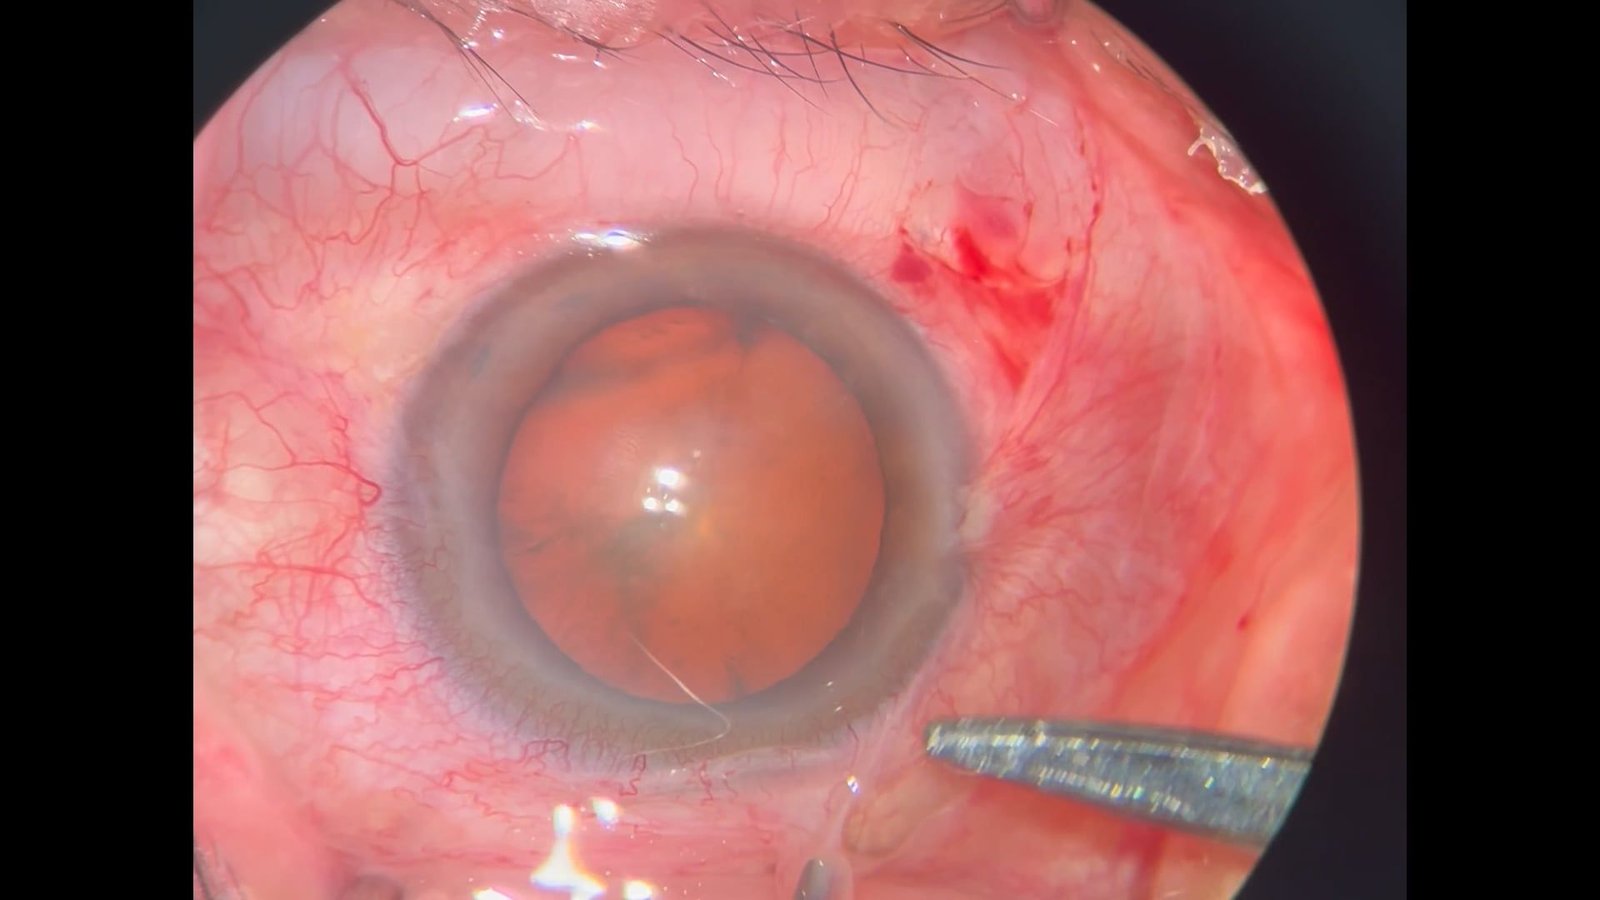

Microspherophakia

Guillermo Amescua